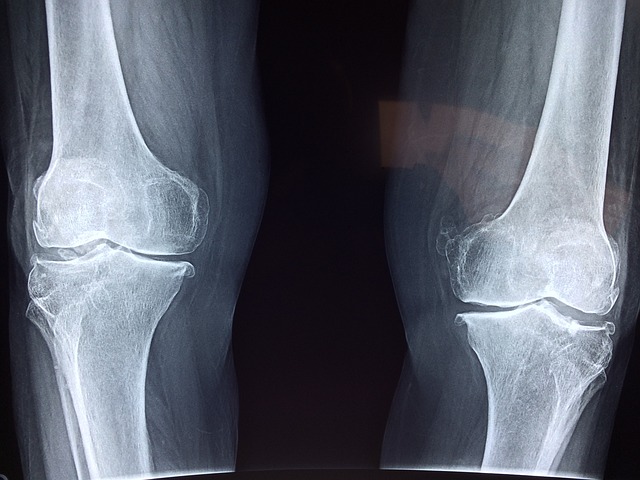

3. 골다공증 예방

아티초크에는 칼륨이 풍부하여 뼈 건강에 도움이 됩니다. 칼륨은 근육과 신경의 흥분 전달과 관련된 중요한 미네랄입니다. 가장 중요한 작용은 세포 내 삼투압 조절로 나트륨의 배출을 촉진하여 염분을 배출하는 것입니다.

칼륨은 고혈압 예방에도 도움이 되지만 소변 중의 칼슘 배출을 억제하는 작용이 있어 골다공증 예방에도 큰 도움이 됩니다. 아티초크에는 마그네슘 함량도 많아 근육과 뼈, 치아 건강에 영향을 미칩니다. 또한 효소 활성 작용이 있어 체내 다양한 대사를 지원합니다.

아티초크의 쓴맛은 시나로피크린 성분으로 항염증 작용과 대사 촉진 작용을 돕습니다. 2017년 연구에 따르면 연골대사를 지지하는 것이 밝혀져 변형성 관절염의 원인인 연골 기질 합성증의 저하 억제를 기대할 수 있습니다.